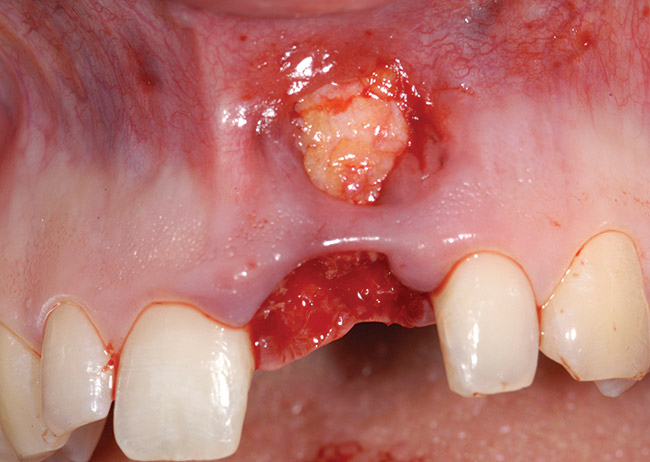

A 26-year-old woman was referred for evaluation and treatment of a fractured maxillary left central incisor. Clinical and radiographic examination revealed a fractured endodontically treated tooth with a fistulous tract in the labial vestibule (Figure 26). Also noted were a flat, thick periodontal biotype, a medium smile line, and a complete loss of labial plate. Atraumatic tooth removal using a periotome and thin-beaked forceps revealed the extent of soft- and hard-tissue loss (Figure 27). Initial treatment consisted of a mineralized bone allograft (MinerOss), along with soft-tissue grafting (connective tissue graft and free gingival graft) (Figure 28 and Figure 29). Reevaluation 9 months later revealed regeneration of a thicker labial plate that was still deficient in both width and height for conventional root-form implant placement. A mandibular block graft harvested from the symphysis was used as Phase II treatment (Figure 30). After 4 months, a root-form implant was placed in a nonsubmerged mode (Figure 31) in preparation for provisional crown fabrication (Figure 32).

Figure 27  Post-extraction socket defect. Note the extent of soft-tissue dehiscence and complete loss of labial plate.

Figure 27